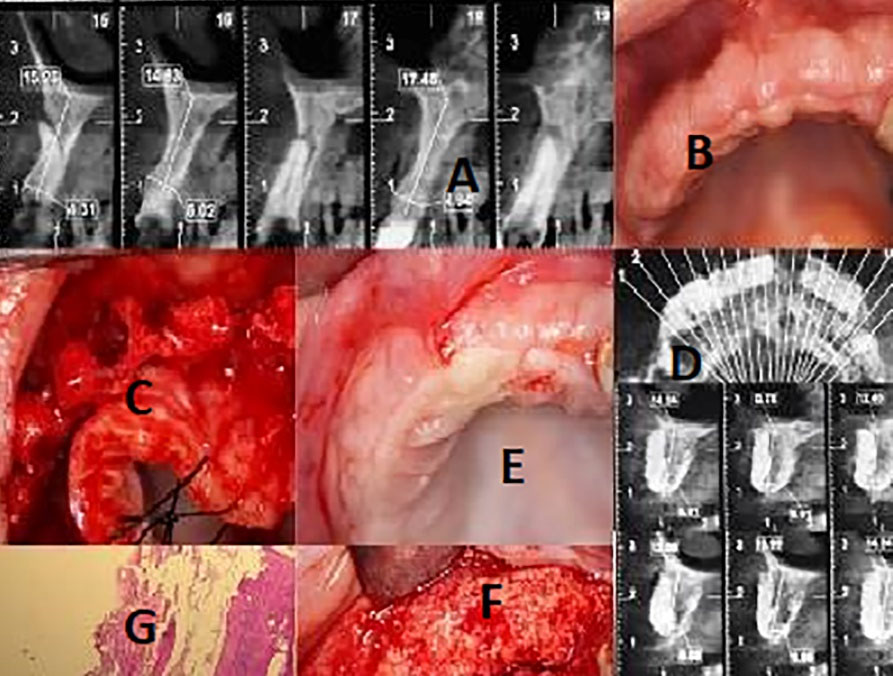

Three consecutive generally healthy patients in a private periodontal office with deficient maxillary alveolar ridge <3 mm in thickness buccolingually were included (Figures 1‒2). The primary defect size and location were assessed using CBCT images (Table 1).

Figure 1.

Case 1: 39-year-old female. a) The initial CBCT at the augmentation phase showing very poor dimensions of the bone (due to the previous traumatic extractions). b) The ridge at the augmentation session. c) Residual ridge following full-thickness flap elevation. d) CBCT of the patient 9 months later shows block integration. e) Clinical view at the implantation session, adequate height, and width of the bone and complete integration of the graft. f) Full-thickness flap. g) While preparing the implant site a trephine biopsy was obtained from the site #16. The biopsy specimen stained by hematoxylin-and-eosin and magnified ×200 shows newly formed bone at the site of implant placement and remnants of the xenograft. Although more remnants and connective tissue might be present at the buccal side, it is of importance that in the favorable site of implant placement only native bone is present.